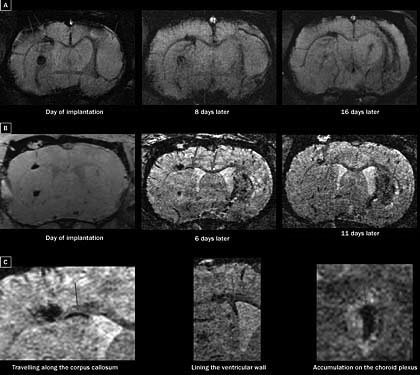

Существует мнение, что следующим шагом в лучевой диагностике будет развитие так называемой молекулярной диагностики (molecular imaging), когда становится возможным очень раннее выявление болезней на основе обнаружения «больных» клеток или молекул. На сегодняшний день эта цель может быть реализована с помощью радионуклидных методов, таких как однофотонная эмиссионная компьютерная томография (ОФЭКТ) и позитронно-эмиссионная томография (ПЭТ), однако возможно использование и новейших методик МРТ (Рис.5). Нет сомнений, что молекулярная диагностика – это ближайшее будущее радиологии. В то же время не следует забывать, что ожидаемый в ближайшие годы переход молекулярной диагностики из лабораторий в клиническую практику не отменит необходимости диагностики «традиционных» заболеваний, например, переломов или пневмоний – с помощью традиционных методов лучевой диагностики.